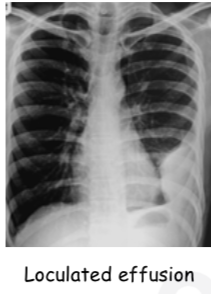

Radiological diagnosis of pleural effusion